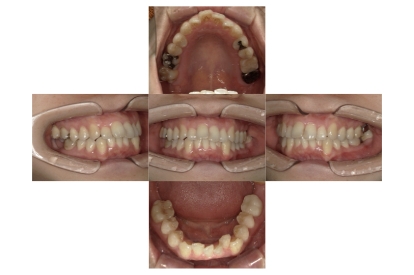

症例3

叢生

抜歯

ブラケット矯正

症例解説

上下顎叢生(上下の前歯のガタガタ)のケースです。

装置はラビアル(上下表側)で、上下顎の小臼歯を4本抜歯を行っています。抜歯したスペースを使って、上下の前歯の後方移動と叢生(ガタガタ)の改善を行っています。

主訴 八重歯を治したい。

年齢・性別 25歳 女性

お住まいの地域 神奈川県川崎市

治療方針 抜歯スペースを利用して上前歯の叢生(ガタガタ)の改善

抜歯部位 上下顎左右第一小臼歯

使用装置 ラビアル(上下表側)、顎間ゴム

治療期間 1年11か月

治療回数 16回

リテーナー クリアリテーナー

BEFORE

AFTER